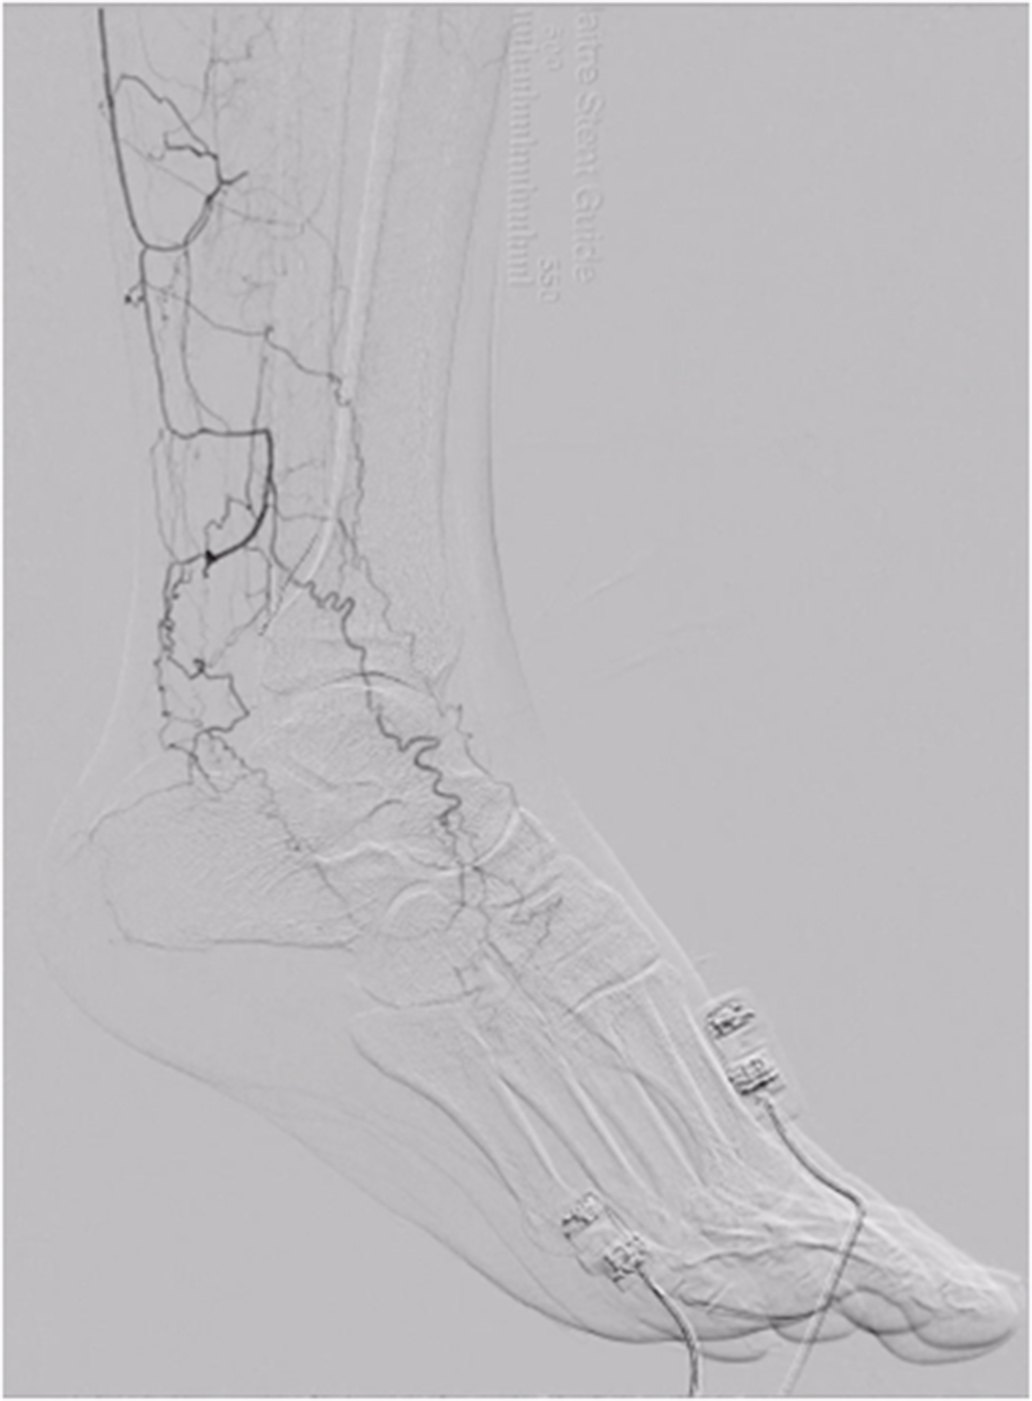

バージャー病

.jpg)